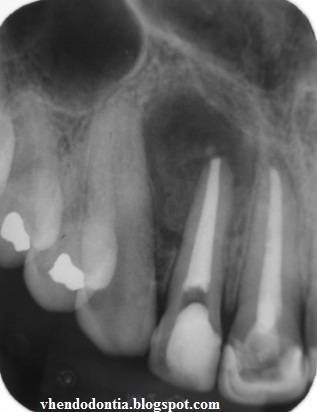

Анатомия: Межкорневая костная перегородка

Раздел: Галерея впечатлений